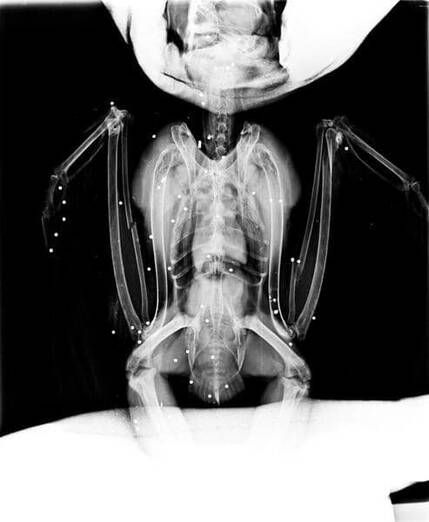

Respecto al búho real, han señalado que fue rescatado por los efectivos de los Agentes Forestales en Villarejo de Salvanés el 4 de febrero, y que el ave presentaba “igualmente una gran cantidad de lesiones”, en este caso producidas por los “más de 40 perdigones recibidos tras ser tiroteado” lo que “indica que fue disparado a corta distancia”, como “reveló también la radiografía que se le realizó antes de ser operado de urgencia” por los servicios veterinarios de GREFA.

El animal presentaba fracturas de cúbito, radio izquierdo y derecho y otras y, “tras una semana en estado crítico” ha empezado a comer por sí mismo, tendrá que ser operado del ojo derecho, si recupera la capacidad de vuelo, lo cual “aún es muy pronto para confirmarlo”, para ser extirpado al haber recibido un perdigón. “Estas aves rapaces pueden seguir cazando con un solo ojo debido a la posición que presentan en la cabeza de este gran depredador ibérico, han resaltado.